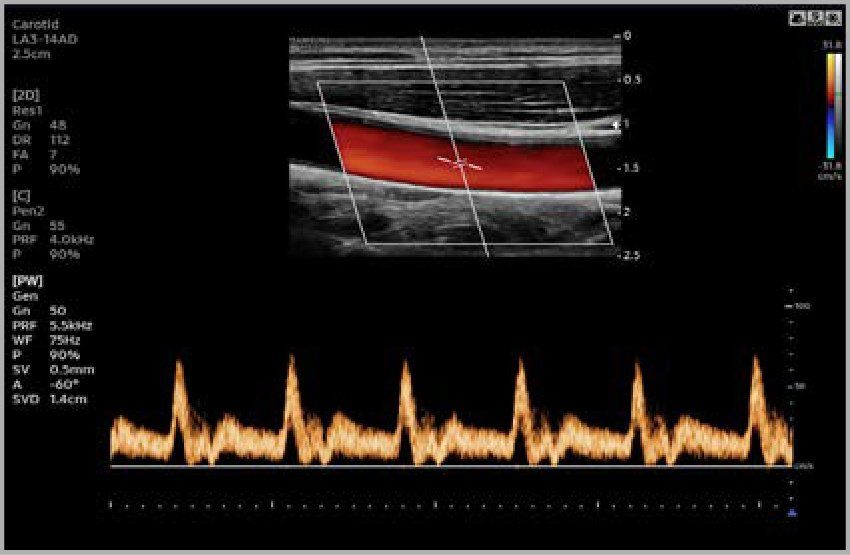

Le ecografie sono, invece, molto utilizzate per lo studio del collo (tiroide, linfonodi), dell’addome (fegato, reni, milza, pancreas, eccetera), della pelvi (vescica, utero, ovaie, prostata), delle vene e delle arterie (carotidi, aorta, eccetera), dell’apparato muscolare (muscoli, tendini, legamenti).

- Ecocolordoppler e Diagnostica Vascolare